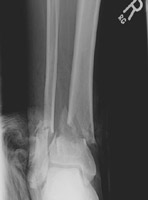

- Click on the image for a larger versionALateral, AP, and oblique radiographs of the tibia and fibula. These reveal mildly displaced spiral fractures of both the tibia and fibula.